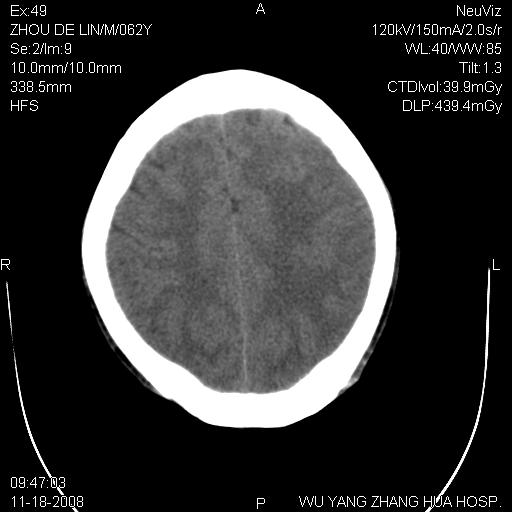

患者近段时间偶有头晕,无其他不适。既往有糖尿病病史。

小脑中线区见一类圆形混杂密度影,四脑室受压变形,其后方见一边界清楚的囊性低密度影,幕上脑室扩张。小脑中线区肿瘤,儿童多见于髓母细胞瘤,成人多见于胶质瘤。

诊断:小脑胶质瘤可能性大。建议增强扫描

支持,病灶似位于四脑室内,不除外四脑室室管膜瘤,发生几率也较高

小脑囊实性占位病变、脑室系统积水扩张、脑肿胀。

小脑囊实性占位病变、脑室系统积水扩张,建议增强

患者4个月前在外地曾做ct<。与本片对比无明显变化(未治疗)。曾在外院做mr,病人未带来,嘱家属改天带来再上传给老师们看看。

诊断:小脑胶质瘤可能性大。建议增强扫描。支持!

1)小脑蚓部(偏左侧)占位性病变;不排除转移瘤可能。建议行进一步检查。2)脑积水。